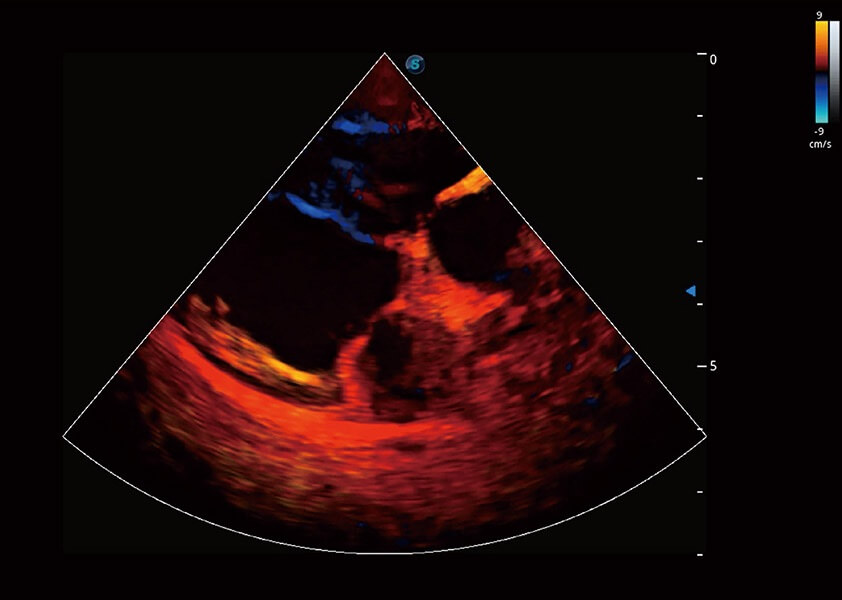

Bright Flow 立体血流成像

在传统二维血流成像的基础上,呈现血流的立体感,具有动感的生命力之美。精确区分不同血管的空间关系,提高了血流的视觉敏感性。

(犬)四腔心血流